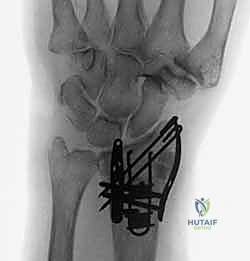

هنا تبرز عبقرية التثبيت المتناسب مع الشظايا (Fragment-Specific Fixation). يعتمد هذا النهج الذي يتقنه الأستاذ الدكتور محمد هطيف على مبدأ بسيط ولكنه معقد في تنفيذه: "لكل شظية عظمية مهمة، غرسة خاصة بها". بدلاً من محاولة إجبار العظم المفتت على التوافق مع صفيحة واحدة كبيرة، يتم استخدام مجموعة من الصفائح الصغيرة جداً (Low-profile mini-plates)، والمسامير الدقيقة، والأسلاك (K-wires) المصممة خصيصاً لتطويق وتثبيت كل عمود أو زاوية تشريحية (مثل شظية العمود الكعبري، أو الحافة الهلالية).

- استقرار ميكانيكي فائق: يوفر تثبيتاً صلباً من زوايا متعددة (Construct stability)، مما يمنع انزياح الشظايا لاحقاً.

- استعادة تشريحية مثالية: يسمح بإعادة بناء السطح المفصلي بدقة متناهية، مما يقلل من خطر التهاب المفاصل التنكسي (خشونة الرسغ).

- حركة مبكرة جداً: بفضل الاستقرار القوي، يمكن للمريض البدء في تحريك أصابعه ورسغه في غضون أيام قليلة من الجراحة، مما يمنع التيبس (Stiffness) ويحافظ على قوة الأوتار.

- غرسات منخفضة السماكة (Low-Profile): الغرسات المستخدمة صغيرة جداً ورقيقة، مما يقلل بشكل كبير من احتكاكها بالأوتار المحيطة، وبالتالي يقلل من خطر التهاب أو تمزق الأوتار بعد الجراحة.

1. المداخل الجراحية (Surgical Approaches)

نظراً لأن الكسر يتم تثبيته من جهات متعددة، قد يستخدم الدكتور هطيف شقوقاً جراحية صغيرة ومدروسة بدلاً من شق واحد كبير.

* المدخل الأمامي (Volar Approach): للوصول إلى الحافة الهلالية والسطح الأمامي لعظم الكعبرة. يتم إبعاد الأوتار والأعصاب (مثل العصب المتوسط) بعناية فائقة.

* المدخل الظهري أو الجانبي (Dorsal/Radial Approaches): شقوق صغيرة إضافية للوصول إلى شظية العمود الكعبري أو الجدار الظهري، مع الحفاظ التام على الأوتار الباسطة.